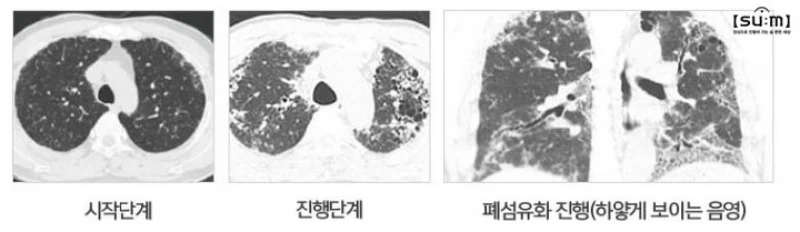

폐섬유증은 흉부 X-ray와 CT 검사를 통해 진단되며, 경우에 따라 흉강경을 통한 조직검사가 필요할 수 있습니다. 폐 기능 검사는 진행 정도를 파악하고 적절한 치료법을 결정하는데 중요합니다.

폐섬유증은 지속적인 폐 손상으로 인해 발견이 어려운 상태까지 진행될 수 있습니다. 이로 인해 치료가 늦춰질 경우 생존율이 낮아집니다.

질병은 수개월에서 수년 동안 진행되며, 호흡곤란이 있는 상태에서 진단되면 통상적으로 3년 이내에 절반 이상의 환자가 사망에 이를 수 있습니다.